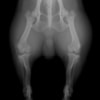

6歳 Mix犬 3.5kg

[主訴]

散歩で駆け出した後にキャンと鳴いてから右後肢を挙上しているとのことで来院。

[検査]

触診検査 MPL左右GradeⅡ

レントゲン検査 にて

右脛骨前方変位あり、ファットパッドサインあり

脛骨公平部角(TPA)の急峻を認める

[治療]

検査結果から前十字靱帯の断裂を疑い脛骨高平部水平化骨切り術(TPLO)を実施することに。また、パテラの安定化のために縫工筋内側広筋切開、滑車溝形成術も併せて実施。

[手術]

前十字靱帯部分断裂

半月板は大きな損傷なし

Fixin T字プレート使用して固定

・術後レントゲン

手術前TPA 28.4° が術後TPA 11.7° に矯正されました。

術後1週間で退院。現在は経過観察中です。

術前TPA計測

手術前

術後TPA計測

手術後

当院ではFixinmicroプレートを使用して小型犬のTPLO手術を実施しております。